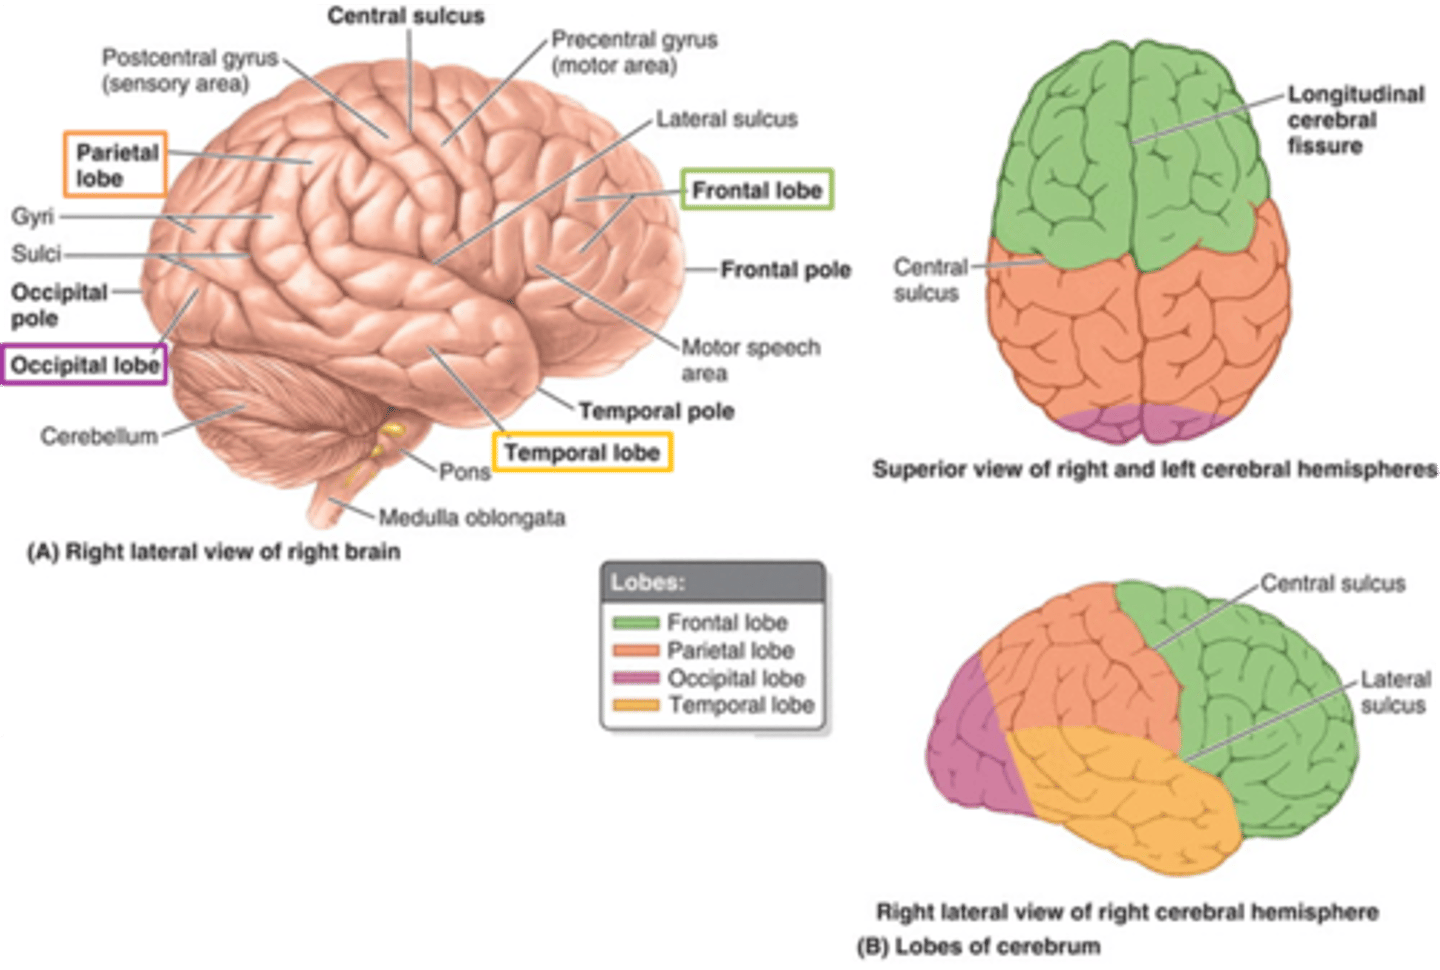

what are the 4 main lobes of the cerebrum?

FPOT

1. frontal

2. parietal

3. temporal

4. occipital

what lobe of the cerebrum is involved with motor and personality?

FPOT

frontal

what lobe of the cerebrum is involved with sensory?

FPOT

parietal

what lobe of the cerebrum is involved in hearing and memory?

FPOT

temporal

what lobe of the cerebrum is involved in vision?

FPOT

occipital

what additional lobe of the cerebrum is involved in receiving, processing, and integrating various types of information (taste, visceral sensation, pain, and balance)?

insula

additional lobe = insula and limbic lobe

what additional lobe of the cerebrum is involved in processing complex aspects of learning, memory, and emotion?

limbic lobe

additional lobe = insula and limbic lobe

which sulcus separates the cerebral hemispheres?

longitudinal fissure

which sulcus divides the frontal lobe from the parietal lobe and divides the precentral and postcentral gyrus?

central sulcus

which sulcus divides the parietal lobe from the temporal lobe?

lateral (sylvian) sulcus/fissure

which sulcus separates the parietal lobe from the occipital lobe?

parieto-occipital sulcus

which gyrus is the primary motor complex?

precentral gyrus

which gyrus is the primary somatosensory complex?

postcentral gyrus